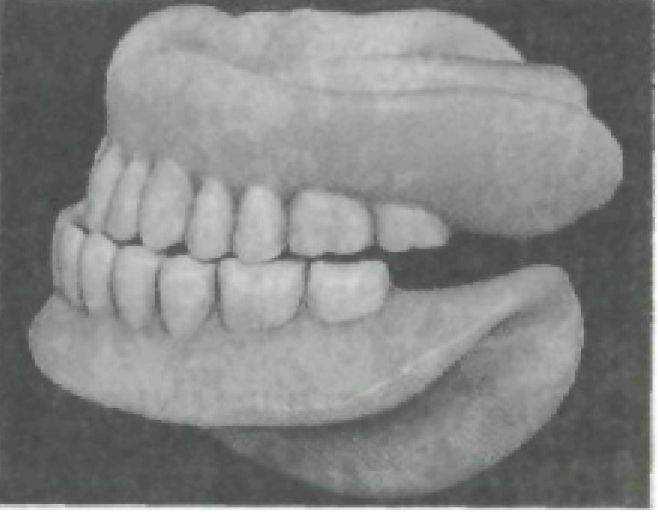

Рис.221. Соотношение зубных рядов при фиксации нижней челюсти со смещением кзади.

Смещение нижней челюсти кзади при определении центрального соотношения челюстей возможно при «разболтанном» суставе. При проверке обнаруживается прогеническое соотношение зубных рядов, бугорковое смыкание боковых зубов, повышение прикуса на высоту бугорков (рис. 221). Устраняется ошибка переопределением центрального соотношения челюстей с новым прикусным валиком на нижней челюсти. Однако это не всегда удается, потому что такие больные довольно часто фиксируют нижнюю челюсть в определенном положении, которое не всегда является правильным.